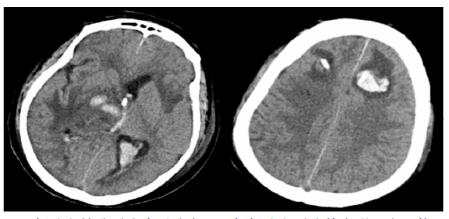

转入ICU后呼吸机辅助通气、甘露醇100 mL/8 h静滴脱水、头孢呋辛1.5 g/12 h静滴抗感染,肠内营养等支持治疗。当晚血常规:白细胞13.3×109/L,中性粒细胞百分比85.3%,C反应蛋白17.1 mg/L,降钙素原0.64 ng/mL。脑室外引流术后次日血化验:白细胞16.6×109/L,中性粒细胞百分比92.8%,C反应蛋白78.4 mg/L;从脑室外引流管留取脑脊液检验:有核细胞6×106/L,红细胞1 960×106/L,蛋白含量1.717 g/L,葡萄糖4.72 mmol/L,细菌培养阴性,涂片未找到细菌;复查头颅CT示:脑室扩张好转,右侧丘脑、左侧岛叶病变伴出血(图 2);胸部CT示,两肺间质性肺炎下叶为著,较前(2019年6月21日)部分好转(图 3)。考虑到炎症指标升高,遂改哌拉西林他唑巴坦3.375 g/12 h静滴抗感染。此后经脑室外引流管反复留取脑脊液送检涂片及培养均阴性。术后第5天行“导航下立体定向颅内病灶活检术+双侧omaya囊置入术”,术中穿刺液呈黄色黏稠脓性,考虑脑脓肿,留取脓液送高通量测序(next-generation sequencing, NGS),并升级为美罗培南2 g/8 h联合利奈唑胺0.6 g/12 h静滴抗感染治疗。术后第7天患者突发血压升高、瞳孔不等大,昏迷程度加深;急查头颅CT示,双侧脑室钻孔引流术后改变,双侧侧脑室引流管走形区出血伴血肿形成;右侧丘脑区积液、积血,双侧脑室积血新发(图 4),甘露醇加量至250 mL/8 h联合地塞米松5 mg/6 h静滴加强脱水;当日术中脓液高通量测序结果回报:皮疽诺卡菌(序列数52 867个)、支气管戈登菌(序列数10个)。确诊脑诺卡菌病,抗菌治疗方案改为亚胺培南西司他丁0.5 g/6 h静滴,联合利奈唑胺0.6 g/12 h和复方磺胺甲恶唑片(0.48 g/片)3片/6 h口服。此后患者仍伴低热,炎症指标呈上升趋势。术后2周患者再次突发血压升高、瞳孔不等大、对光反射消失、神志深昏迷,急查头颅CT示再发脑疝(图 5),急诊行“去骨瓣减压术+脑内血肿清除术”,术后患者仍呈深昏迷状态,双侧瞳孔散大、对光反射消失,次日自动出院。

| 双侧脑室钻孔引流术后改变,双侧侧脑室引流管走形区出血伴血肿形成;右侧丘脑区积液、积血,双侧脑室积血新发 图 4 患者2019-10-06头颅CT结果 |

| 双侧侧脑室引流管走形区出血伴血肿形成;右侧丘脑区积液、积血,脑室积血;左引流管旁血肿较前(2019-10-06)增大,脑室积血增多,中线右移。左岛叶及颞叶斑块状低密度影 图 5 患者2019-10-13头颅CT平扫结果 |